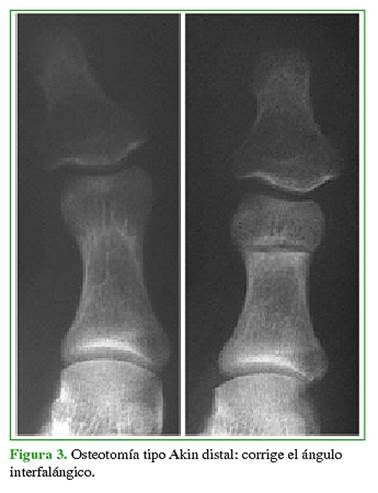

En mayoría de los casos, se recurre a las osteotomías para tratar el hallux valgus. En 1925, Akin13 describió un procedimiento para el hallux valgus que incluía la resección de la exostosis medial del primer metatarsiano, una osteotomía de resección en cuña de base medial en la base de la falange proximal del hallux y la liberación lateral del tendón abductor. Esta osteotomía falángica se popularizó como osteotomía de Akin, y fue descrita en la base de la falange proximal del hallux para la corrección del DASA (distal articular set angle) (Figura 2). Una variación de la osteotomía de Akin consiste en realizarla a nivel distal para corregir el hallux valgus IF (Figura 3). Se lleva a cabo en forma percutánea con técnica mínimamente invasiva.